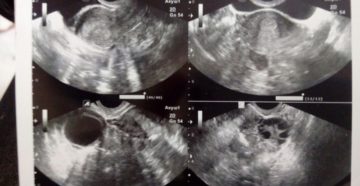

Что нужно знать о сердцебиении у плода Врачи следят за сердцебиением плода на протяжении всего…

8 неделя беременности Уверенными шагами двигаемся к окончанию первого триместра. Не верите, что наступила 8-я…